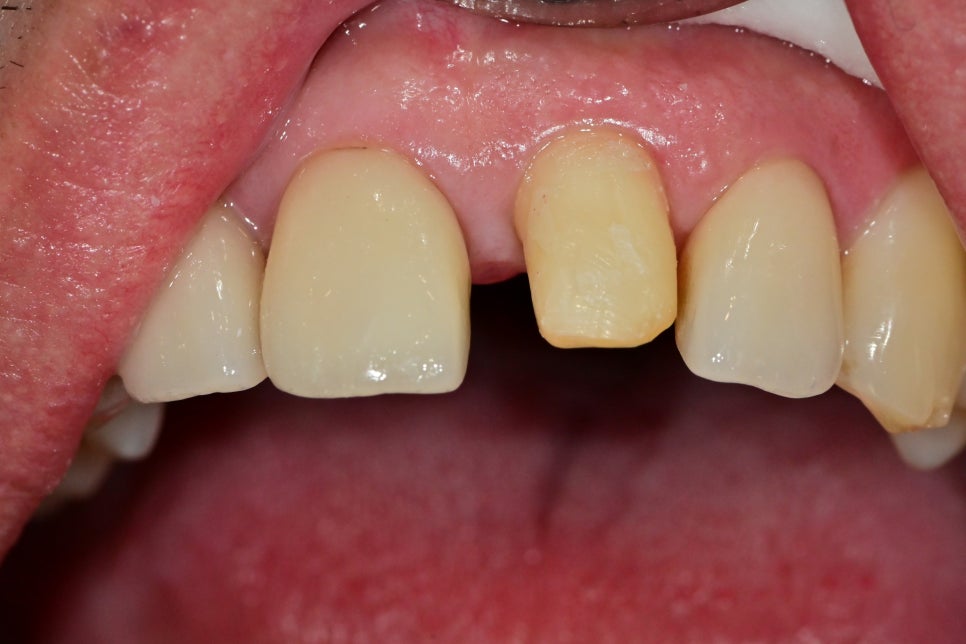

제거는 어렵지 않게 할 수 있었습니다.

제거 후 치아의 사진입니다.

치아의 각도가 살짝 바깥으로 나온 걸 보면

모양을 잡기 위해 최소한 삭제를 해서 얇게 제작한 케이스인데

유지와 각도를 다시 잡기 위해 조금만 다듬고 크라운 제작에 들어갔습니다.